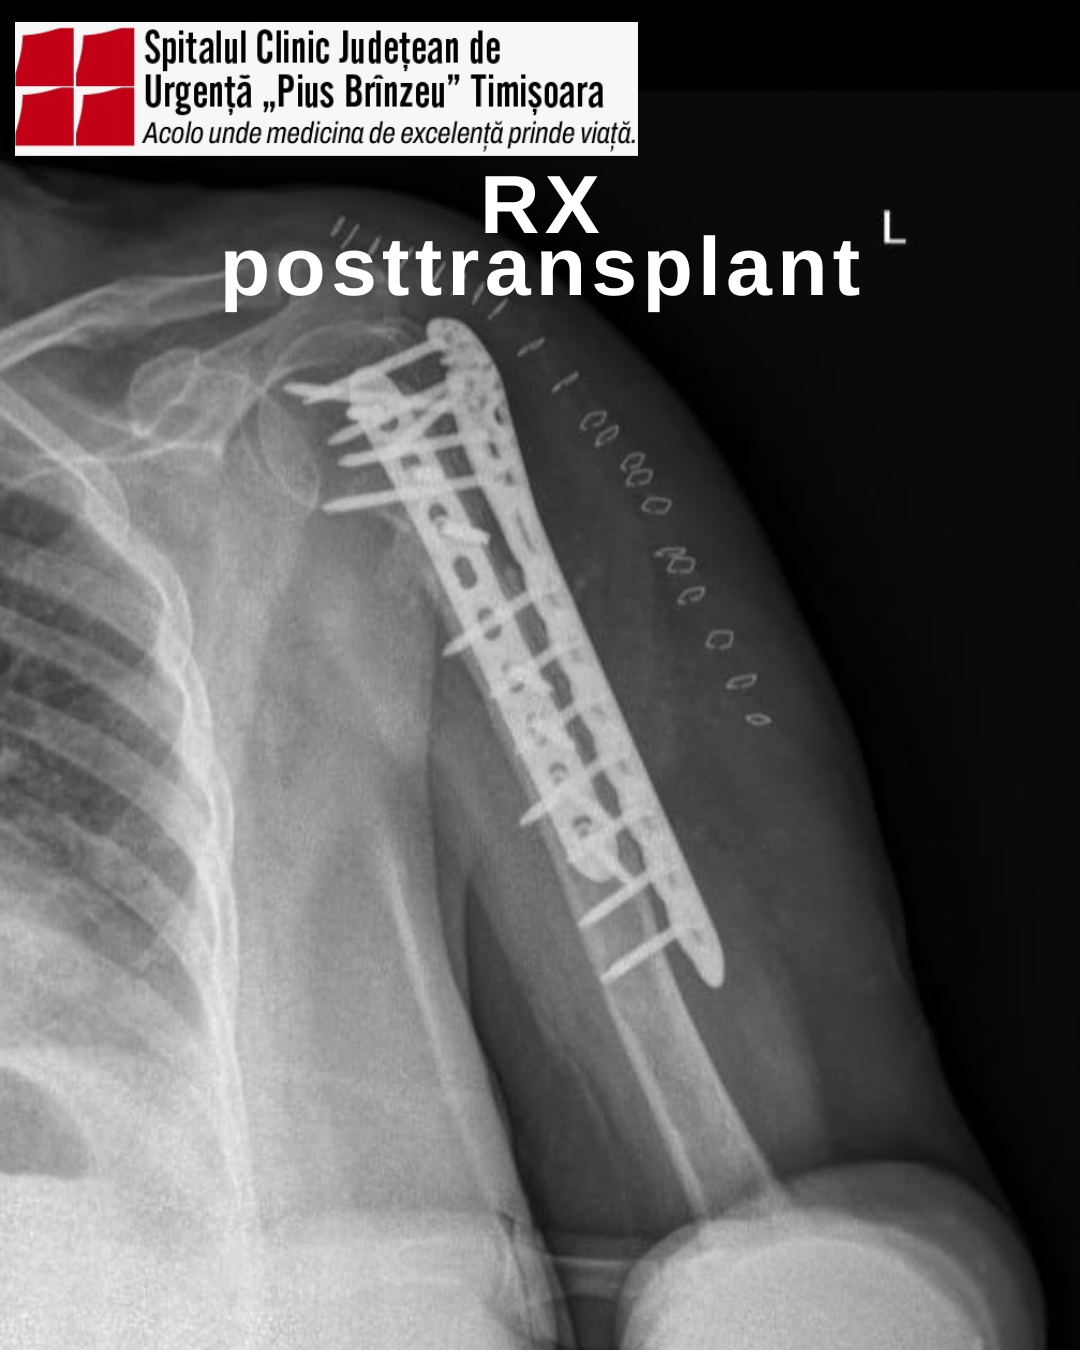

Intervenția chirurgicală a constat în cura chirurgicală a unei fracturi iterative de humerus proximal, asociată cu defect osos semnificativ și degradarea materialului de fixare utilizat la intervenția chirurgicală inițială. Complexitatea cazului a impus adoptarea unei soluții terapeutice avansate, menită să ofere pacientei cele mai bune șanse de recuperare.

Astfel, s-a realizat augmentare biologică cu alogrefă structurală de peroneu, urmată de fixare internă prin tehnica „double plating”.